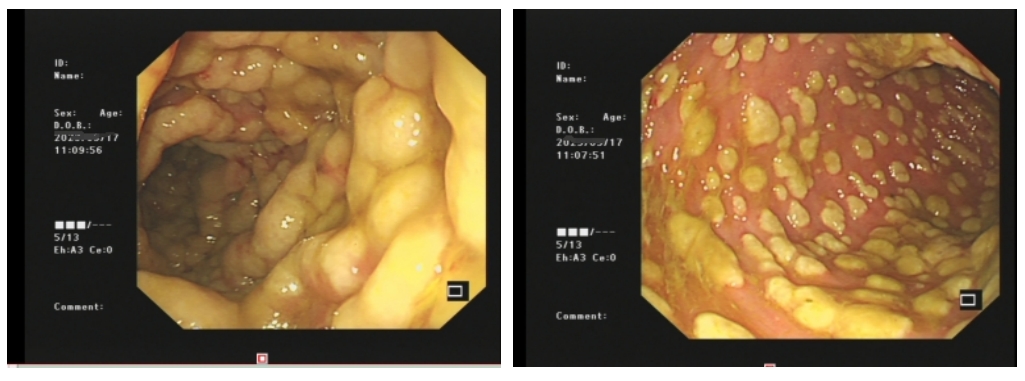

该患者既往有“宫颈癌手术及放疗;尿毒症”病史,曾于当地诊所多次使用抗菌药物。肠镜检查结果显示:镜下可见结肠黏膜充血水肿、糜烂,表面覆有多发、大小不一的丘状黄白色伪膜,疑似伪膜性肠炎。

内镜检查:粘膜发红水肿,伪膜呈斑片状或地图状,跳跃性分布。